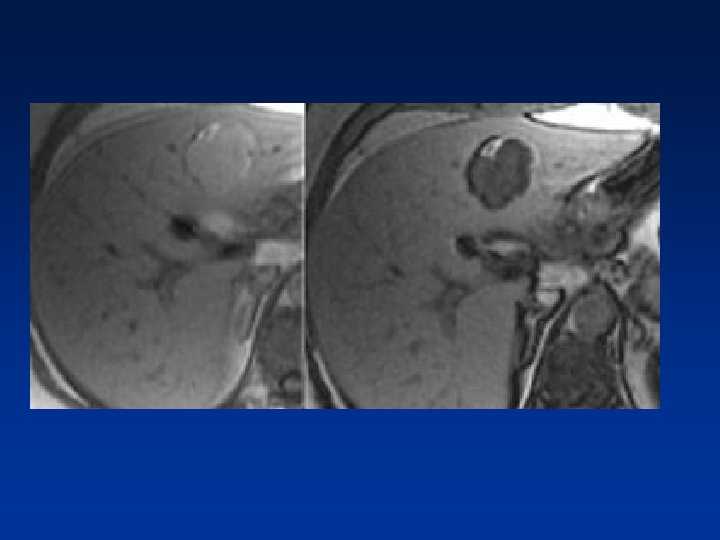

• T 2 W, T 1 W without gadolinium and a delayed phase after gadolinium.

• FNH seen as hypervascular lesion in the late arterial phase & isodense in the portal venous phase. No scar was seen.